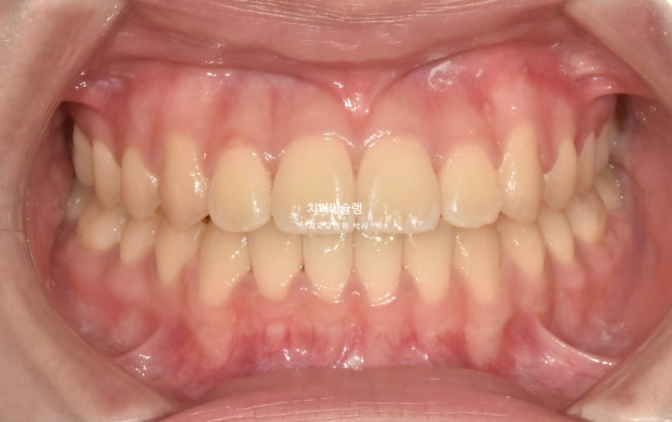

24.07

치료시작 1년째 모습입니다.

아래는 23년 9월에 클리피씨 장치를 부착하고 윗니는 24년 4월에 처음 장치를 붙였습니다.

치료 시작 8개월 차에 위 치열 교정을 뒤늦게 시작한 셈입니다.

아래는 교정용 나사를 심어 사랑니 공간으로 전체치열을 후방이동 시키는 중입니다.